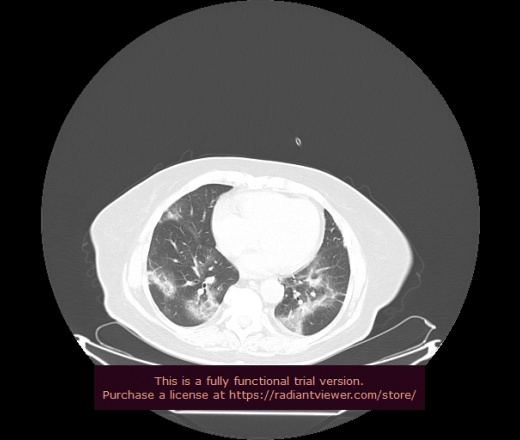

Уважаемые коллеги, если имеется интерес, сможете ли Вы спрогнозировать дальнейшее +-одинаковое течение процесса у 4 данных разных пациентов? Зацепиться где-то можно очень просто, где-то нельзя.